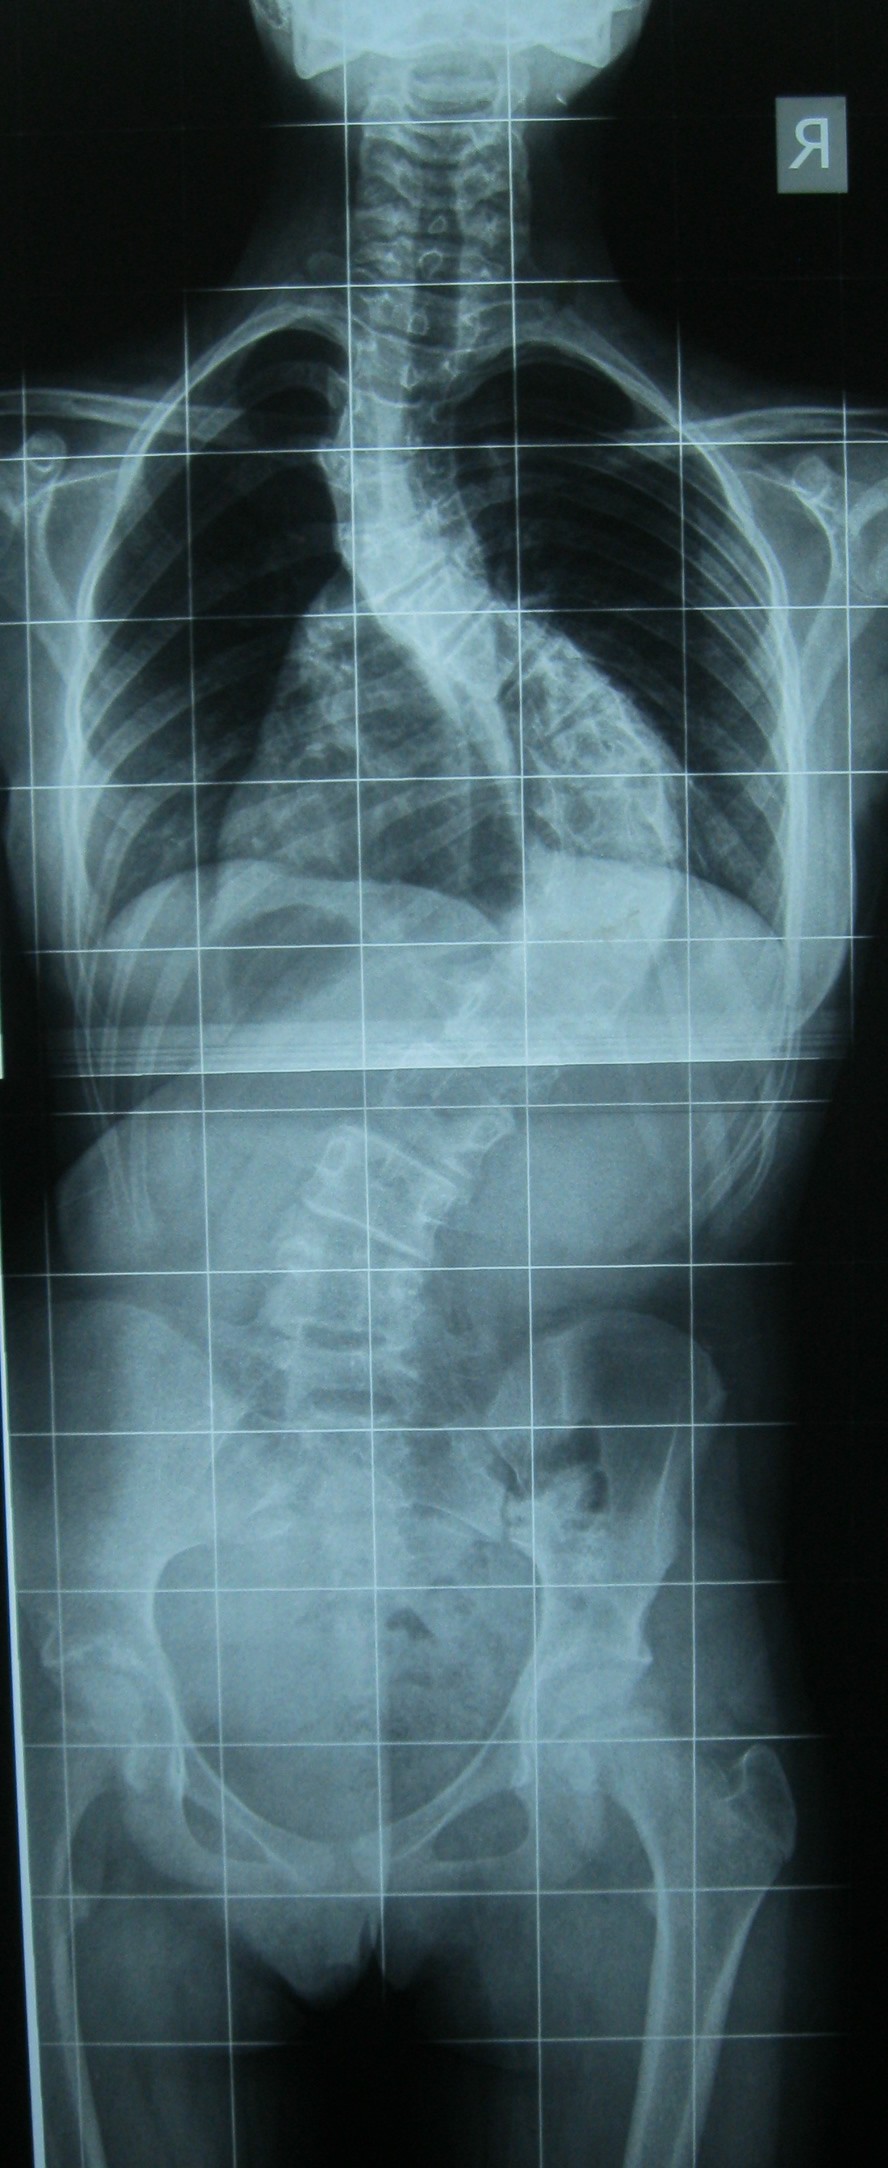

Farklı tipte skolyozu olan hastaların ameliyat öncesi ve sonrası fotoları: